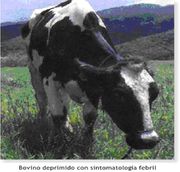

| 12:38 13 dic 2018 | Rabia Paralitica Bovino.jpg (archivo) |  |

52 KB | 1 | |